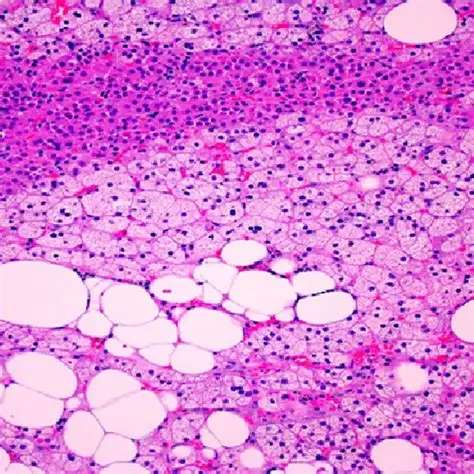

Ao testarem retirar a proteína do organismo de camundongos, eles descobriram que, na realidade, os animais desenvolveram o distúrbio contrário, a lipodistrofia. A condição é marcada por perda de massa gorda e leva a riscos de distúrbios metabólicos tão graves quanto a obesidade.

A equipe investigava inicialmente a localização correta da proteína e descobriu que ela aparece em gotículas lipídicas e também no núcleo de adipócitos. Nesse ambiente, a HSL interage com outras moléculas e colabora com mecanismos de manutenção do tecido adiposo.

O processo descoberto por eles revela que a adrenalina ativa a HSL e estimula a saída da proteína do núcleo das células de gordura durante períodos de jejum. Em camundongos obesos, há uma concentração no núcleo, como se as proteínas lá presas não pudessem iniciar o processo de queima de gordura.

Os resultados apontam que adipócitos defeituosos resultam tanto em obesidade quanto em lipodistrofia. As duas condições provocam falhas de regulação metabólica e ampliam o risco cardiovascular, mostrando como um quadro aparentemente oposto de saúde pode compartilhar tanto origem como riscos.